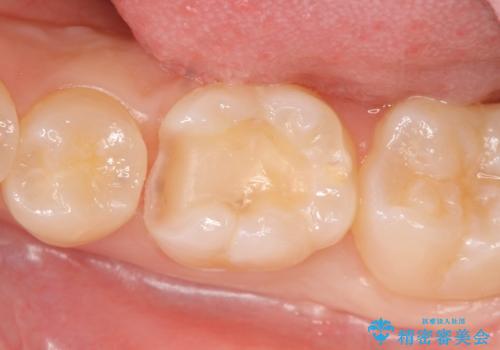

- 左下奥歯がしみるので診て欲しいといらっしゃった方の症例です。

古い樹脂と虫歯を除去後、セラミックインレーによる修復を行いました。